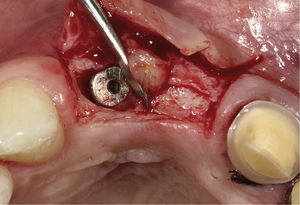

Secuencia de tratamientoEn otoño de 2007 se retiraron las coronas implantosopor-tadas cementadas con cemento provisional y los pilares 11 y 12 y, después de una limpieza minuciosa, se cerraron los implantes con tornillos de cierre. Se obtuvieron dos injertos de tejido conjuntivo de la zona de la tuberosidad maxilar y se colocaron bajo un colgajo de espesor par-cial y desplazamiento coronal. Se confeccionó una pró provisional de acrílico con refuerzo metálico y se cementó por medios adhesivos (figs. 6 y 7).

Con objeto de cubrir la dehiscencia residual e incre-mentar el volumen del tejido se practicó al cabo de 3 me-ses otro aumento con dos injertos de tejido conjuntivo procedentes del lado derecho e izquierdo del paladar (figs. 7 a 9). Transcurridos otros 3 meses se expuso el implante 12 mediante un colgajo de desplazamiento y se realizó un nuevo aumento de tejido blando. Se preparó el diente 21 para la colocación de una prótesis provisional y se retiró el pilar antiguo del implante 22 (figs. 10 a 12). Se colocaron pilares nuevos individualizados y angula-dos, fabricados con una aleación de alto contenido en oro. También se colocó el puente provisional 12-22 fabrica-do en el laboratorio. Aunque se había logrado mejorar considerablemente el volumen del tejido blando y con-formar el asiento del póntico 11, persistió un déficit de la papila de los dientes 11-12 que no se logró corregir de forma notoria ni siquiera con un nuevo aumento local en esta zona.